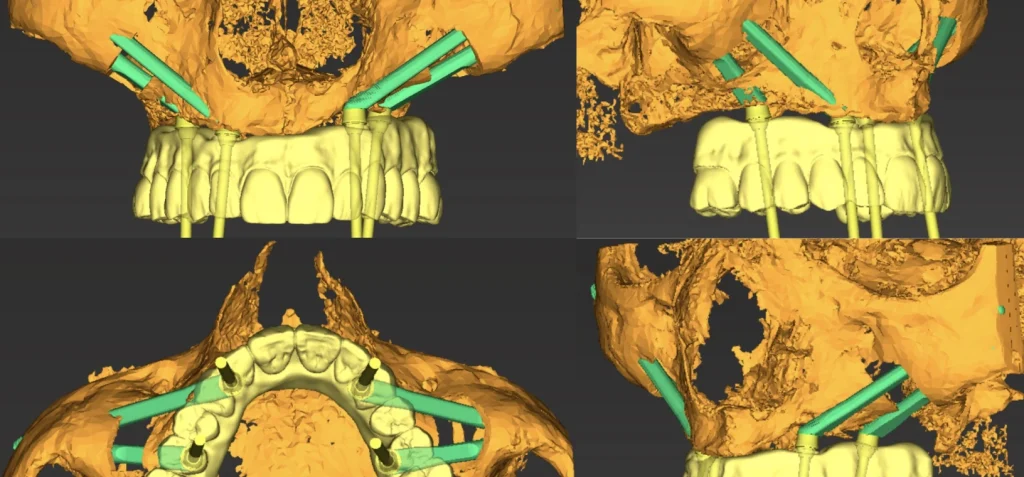

L’étude implantaire se fait à l’aide d’un logiciel de planification qui intègre le design de la future prothèse qui a été validé d’un point de vue esthétique et fonctionnel pour optimiser le placement des implants. Une fois validé un guide chirurgical en titane imprimé monobloc, est conçu pour reproduire lors de la chirurgie la position virtuelle des implants planifiés gage de plus de précision et de sécurité chirurgicale. C’est un guide à double douille qui stabilise le foret lors du passage dans le maxillaire puis dans le zygoma. L’extension zygomatique du guide est retirée après le forage pour laisser passer l’implant zygomatique guidé.